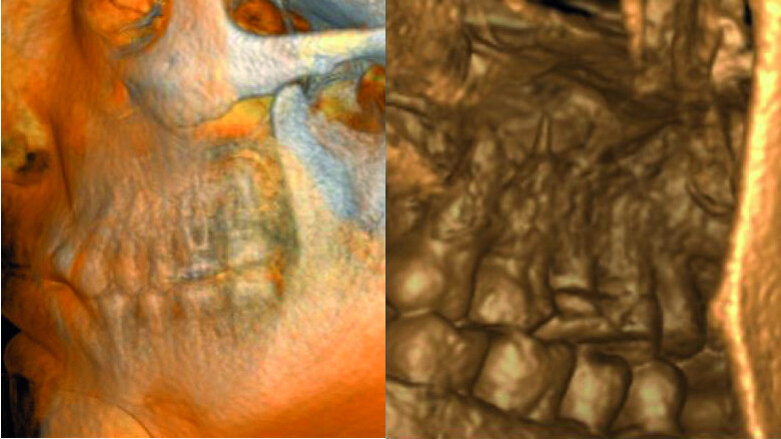

The patient was referred for a dull pain affecting a maxillary molar. On the preoperative radiograph, we could see a diversity of obturation materials, including single cones, resin cement and silver cones, with some of them already fragmented and one piece protruding from the root. Looking closely at the sinus and the sinus membrane, we could see that the membrane had been perforated by the inflammatory/infection process, which had led to sinus infection (Fig. 15).

Under the operating microscope and using ultrasonic and K3XF rotary files (Kerr Dental), I managed to clear the root system of all the previous obturation materials, and placed a dry cotton pellet and temporary cement, as the patient had become tired during this long appointment (Fig. 16). Figure 17 shows some minor debris of silver cones that had passed beyond the mesial apex and using the MacroCannula of the EndoVac, I managed to retrieve one small piece of the silver cone and to complete the chemical cleaning of the root canal system.

Figure 18 shows the immediate postoperative situation, focusing on the obturation of the mesial canals, and a slight improvement of the membrane and the sinus is evident. Figure 19 shows the three-month follow-up with an almost complete closure of the membrane and the bone of the sinus floor.